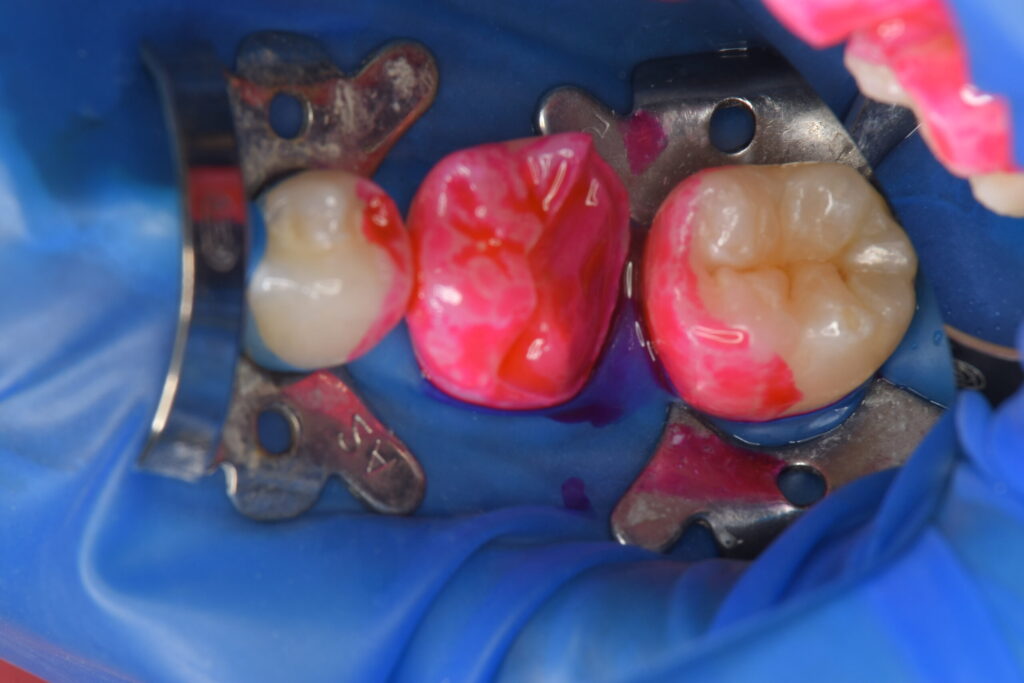

合い具合を確かめ、問題がないためラバーダム防湿を行い清潔な状態を作っていきます。

染め出しを行い、余分な汚れをブラシとブラスターで飛ばしていきます。